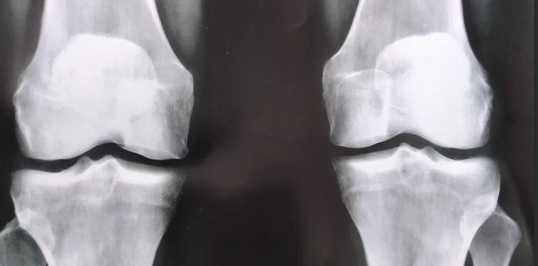

Рентгенограмма, КТ, МРТ при отрывной травме колена

Рентгенография и КТ при переломе костей - что покажет

Рентгенография и КТ костей являются аппаратными методами диагностики перелома костей. Исходя из первичных симптомов, истории болезни, противопоказаний и диагностических целей, врач травматолог назначает необходимые способы обследования. В большинстве случаев, рентгенография костей выбирается как первичный метод диагностики. Если результаты исследования носят тревожный или неясный характер, дополнительно назначается:

Принцип рентгенографии и ее более современного аналога компьютерной томографии основан на рентгеновском излучении. Оно в разной степени поглощается тканями организма, и наибольшее поглощение происходит в костных структурах и легких. Поэтому эти методы часто используются, чтобы выявить патологии скелета и дыхательной системы — на полученных снимках можно достаточно легко рассмотреть множество отклонений от нормы:

- повреждения скелетных костей — переломы, трещины;

- травматические изменения анатомии суставов — вывихи, подвывихи;

- врожденные аномалии суставов;

- отложения солей и остеофиты в полости суставов;

- метастатические поражения в костях и другое.